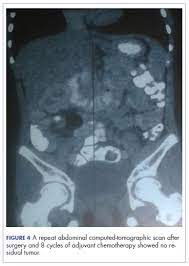

All Colon Cancer Articles Everyday Health from images.everydayhealth.com Learn more about potential signs of colon cancer. Symptoms could be caused by other conditions, but they could also be signs of cancer. In other words, the signs and symptoms can occur due to a number of different conditions. Surgical resection may be curative alth. Early signs of colon cancer include having frequent bouts of diarrhea or constipation or any abnormal changes in your bowel bowel movements. Colon cancer is the third most common cancer in men and women across europe and the usa. Many symptoms can indicate colon cancer, but if someone has these symptoms, it does not necessarily mean that they have this disease. Ct and mri are the modalities most frequently used for staging.

If you have any rectal bleeding or blood in the stool, tell your doctor as soon as possible. Colon cancer is one of the most common cancers in both men and women. Colon cancer is the third most common cancer in men and women in the u.s. Symptoms and signs of colon cancer can include (2): The chance of getting this disease increases with age. Having any one of these signs of colon cancer does not necessarily mean that you have it but obviously the more signs that you have the more likely it is. Learn the signs and symptoms of colon cancer in this video with dr. Screening tests can find precancerous polyps, so they can be removed before they turn into cancer. Learn the symptoms of stage iv colon cancer and which tests your doctor uses to find the right treatment. Perforation tumor perforation is an uncommon complication of colorectal cancer, but one that is. Signs and symptoms of colon cancer in men. Symptoms of colon cancer include changes in bowel habits and unexplained abdominal pain. Ct and mri are the modalities most frequently used for staging.

According to the centers for disease control (cdc), 51,783 americans died from colon cancer in 2011 (the most recent year for available data). Signs and symptoms of colon cancer include: However, the exact cause of this cancer is unknown but it may develop when the healthy cells turn to abnormal. Colorectal cancer signs & symptoms. The colon is divided as shown in figure 1. Colorectal cancer almost always develops from precancerous polyps (abnormal growths) in the colon or rectum. Most patients did not have a relevant past medical or family history, with the suggestion that these cases arise as a result of spontaneous genetic mutation. Colon cancer is the third most common cancer in men and women across europe and the usa. Colorectal cancer (crc) is one of the most aggressive cancers worldwide. Colon cancer is the third most common cancer in men and women in the u.s. Ct and mri are the modalities most frequently used for staging. Signs and symptoms of colon cancer in people under 45. The earlier colorectal cancer can be found, the more likely it can be successfully treated.